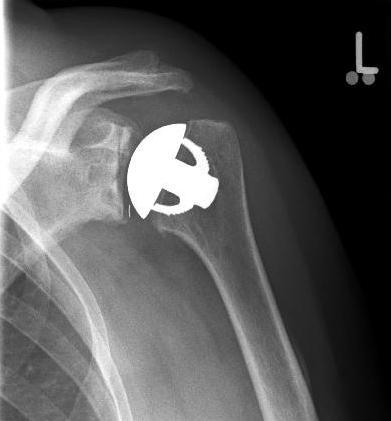

Abbildung9Abbildung10 Special prostheses such as an inverse shoulder prosthesis (syn.: "Delta prosthesis", "Grammont prosthesis") for the combination of severe omarthrosis with joint instability and rotator cuff defects

Right: radiograph of an inverse shoulder prosthesis for rotator cuff defect arthropathy.

left: Inverted shoulder prosthesis (Aequalis reversed type, Tornier company).